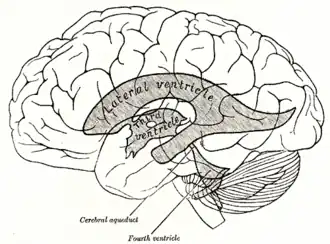

| Drawing of the ventricular system from Gray's Anatomy, with third and fourth ventricles and the aqueduct of Sylvius (cerebral aqueduct) labeled | |

Aqueductal stenosis is a narrowing of the aqueduct of Sylvius which blocks the flow of cerebrospinal fluid (CSF) in the ventricular system. Blockage of the aqueduct can lead to hydrocephalus, specifically as a common cause of congenital and/or obstructive hydrocephalus.[1][2]

The aqueduct of Sylvius is the channel which connects the third ventricle to the fourth ventricle and is the narrowest part of the CSF pathway with a mean cross-sectional area of 0.5 mm2 in children and 0.8 mm2 in adults.[3] Because of its small size, the aqueduct is the most likely place for a blockage of CSF in the ventricular system. This blockage causes ventricle volume to increase because the CSF cannot flow out of the ventricles and cannot be effectively absorbed by the surrounding tissue of the ventricles. Increased volume of the ventricles will result in higher pressure within the ventricles, and cause higher pressure in the cortex from it being pushed into the skull. A person may have aqueductal stenosis for years without any symptoms, and a head trauma, hemorrhage, or infection could suddenly invoke those symptoms and worsen the blockage.[4]

Signs of aqueductal stenosis other than those mentioned in “Causes of stenosis” include detection of an enlarged lateral and third ventricle in conjunction with a smaller fourth ventricle. This variation in ventricle size is indicative of a blockage in the aqueduct because it lies between the third and fourth ventricles. Another sign of stenosis is deformation of the midbrain, which can be severe. This is caused by the pressure gradient formed from a blockage in the aqueduct.[3]